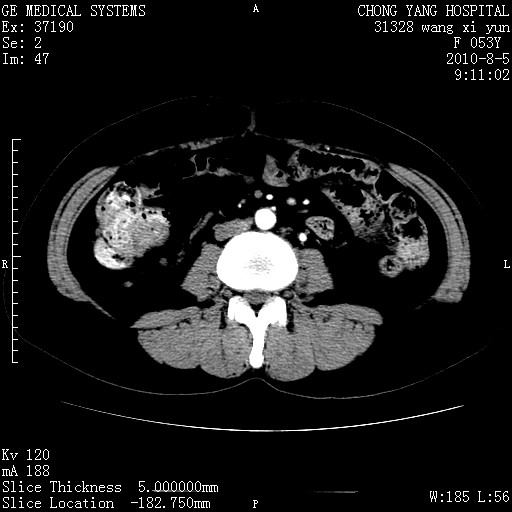

标题: CT28214:F41Y 血尿二十天,建议盆腔平扫加增强。

片子搞错了吧?和上一个是同一张片子。

胆管细胞ca?

1)考虑肝左叶胆管细胞癌。2)脂肪肝。

支持胆管细胞ca。